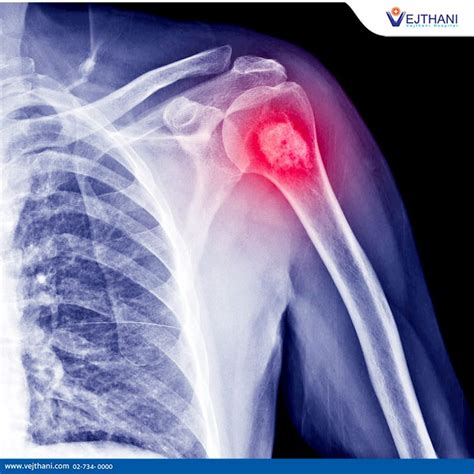

So, you’ve noticed some concerning symptoms, and you’re wondering, “What happens next?” This is where the diagnosis and staging of osteosarcoma come into play, and it’s a critical part of the whole process, as highlighted by the American Cancer Society. Getting a clear diagnosis is the first hurdle, and then understanding the stage helps doctors figure out the best treatment plan. The diagnostic journey usually begins with a thorough physical examination and a detailed discussion about your medical history and symptoms. After that, imaging tests are key. X-rays are often the very first step. They can show abnormal changes in the bone, like a tumor or a fracture. If an X-ray suggests a possible bone tumor, then more advanced imaging techniques are usually ordered. CT scans (Computed Tomography) are excellent for providing detailed cross-sectional images of the bone and surrounding soft tissues. They can help doctors see the size of the tumor and if it has invaded nearby structures. MRI scans (Magnetic Resonance Imaging) are also very important. They give even more detailed images, especially of soft tissues, and are particularly good at showing how far the tumor has spread into the bone marrow or into nearby muscles and blood vessels. Bone scans might also be used. In this test, a small amount of radioactive material is injected into a vein, and it accumulates in areas of increased bone activity, which can highlight the tumor and also show if cancer has spread to other bones. To confirm that it is indeed osteosarcoma and not some other condition, a biopsy is essential. This is where a small sample of the suspected tumor tissue is removed, either through a needle biopsy or a surgical biopsy, and examined under a microscope by a pathologist. The pathologist looks for the characteristic malignant bone cells that define osteosarcoma. This step is absolutely crucial because it confirms the diagnosis and helps determine the specific type and grade of the tumor, which impacts treatment decisions. Once osteosarcoma is confirmed, the next step is staging . Staging is the process of determining the extent of the cancer – how large the primary tumor is, whether it has spread to lymph nodes, and if it has metastasized to distant parts of the body, most commonly the lungs. The American Cancer Society explains that staging helps doctors predict the prognosis and plan the most effective treatment. The most common staging system used for osteosarcoma is the TNM system (Tumor, Node, Metastasis), but for bone cancers, surgeons often use a system that categorizes tumors based on whether they are contained within the bone (localized) or have spread outside the bone (regional or distant). The grade of the tumor is also a critical factor. Tumor grade refers to how abnormal the cancer cells look under a microscope and how quickly they are likely to grow and spread. High-grade tumors are more aggressive and have a poorer prognosis than low-grade tumors. The stage and grade together give doctors a comprehensive picture of the cancer’s status. For example, stage I cancers are typically low-grade and localized, while stage IV cancers have likely metastasized. The American Cancer Society provides detailed information on these stages, helping patients and their families understand what each means for their treatment journey. This detailed diagnostic and staging process is fundamental for tailoring a personalized treatment approach, which is vital for maximizing the chances of successful outcomes in the fight against osteosarcoma.